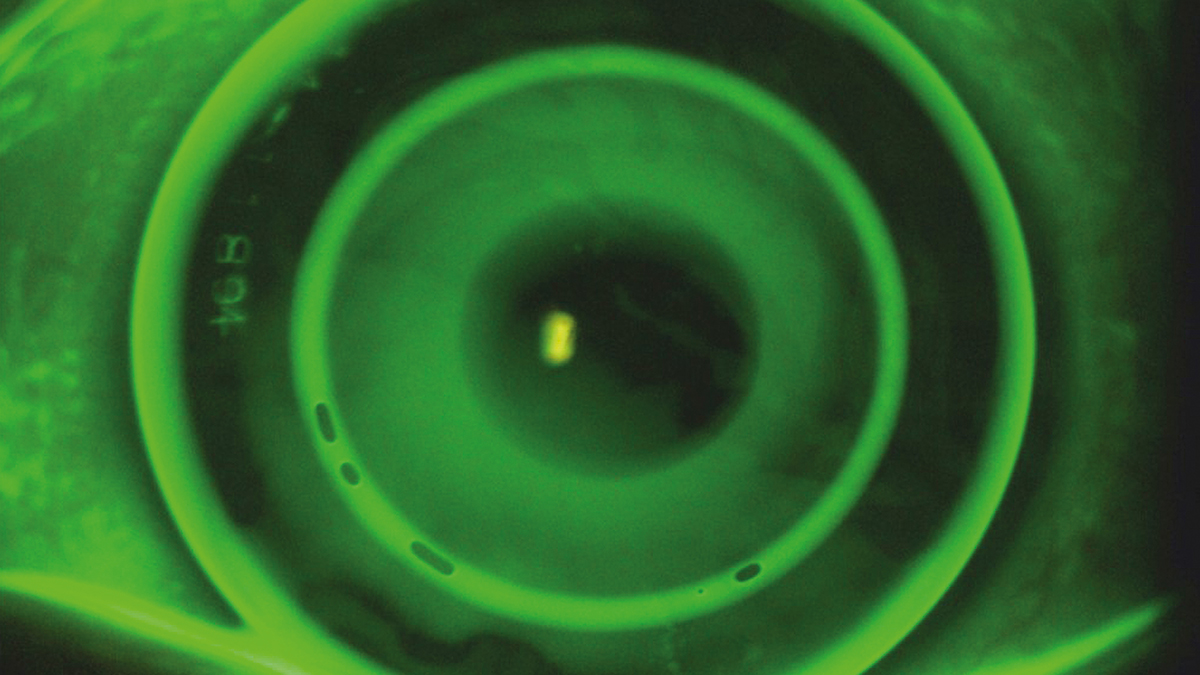

Die Juli/August-Ausgabe der OCL behandelt das Thema Orthokeratologie. Auf dem Titelbild zu sehen: ein Fluoreszeinbild der multifokalen Ortho-K.